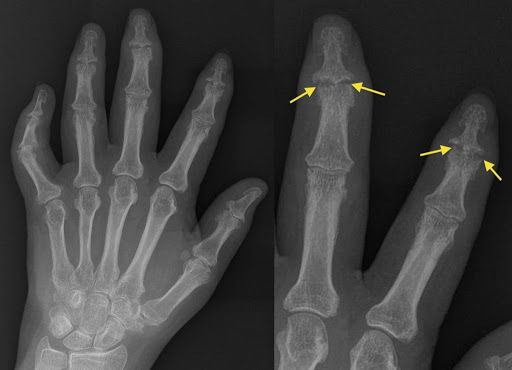

List three x-ray features of psoriatic arthritis